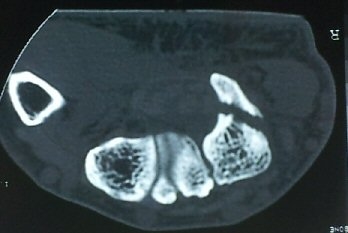

¼ÒÁö±¸ ³»Ãø¿¡ ȾÀ¸·Î ŽÃËÀÚ¸¦ ´ë¾î °¥°í¸®»À °¥°í¸® ³»Ãø¸é ÇÇÁú°ñÀ» °üÂûÇÏ´Ï(¾Æ·¡ ±×¸²)

°¥°í¸® ÇÇÁú°ñ ¿¬¼Ó¼º ¼Ò½Ç(loss of cortical continuity of hook of hamate)ÀÌ °üÂûµÈ´Ù(±×¸² 1, 2).

ÇÇÁú°ñ ¿¬¼Ó¼º ¼Ò½ÇÀº °ÇÃø°ú ºñ±³ÇØ¸é ´õ¿í ¶Ñ·ÈÇÏ´Ù(±×¸² 3, 4).